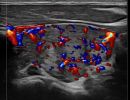

Με την τριπλή μελέτη του Θυρεοειδούς Αδένα, που περιλαμβάνει το B-Μode, το Έγχρωμο Υπερηχογράφημα και την Ελαστογραφία, γίνεται μια ολοκληρωμένη χαρτογράφηση του θυρεοειδούς αδένα. Το περίγραμμα, η αγγείωση και η ελαστικότητα του αδένα, καθώς και η υφή μίας πιθανής βλάβης αξιολογούνται με ακρίβεια και αξιοπιστία.